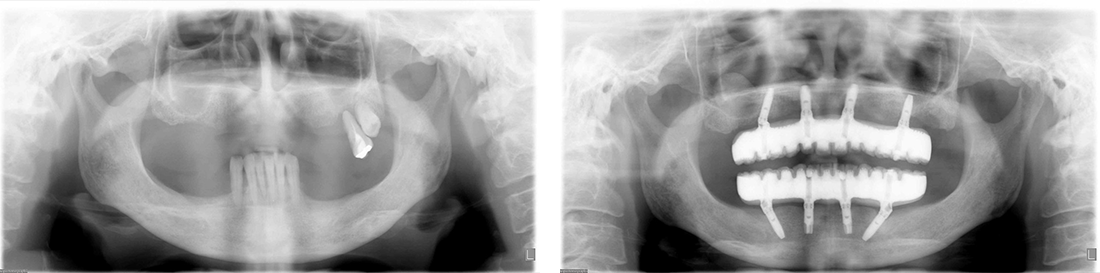

All-on-4症例 Case1

Treatment cases

Before

After

インプラント治療は、咀嚼機能の改善だけでなく、 口腔周囲筋の発達により見た目の若返りにも貢献してくれます。